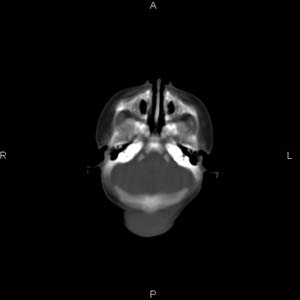

患者男,27天,出生后正常,今天中午在母亲怀里抱着吃奶在放下睡觉时发现后枕部慢慢出现一包块,来查头颅ct。无外伤史。包块内ct值47-51hu。请大家讨论。

皮下血肿,颅骨无缺如 ,颅缝无增宽。皮下血管破裂所因起。

头皮下血肿,局部枕骨略有凹陷

支持脑膜脑膨出,双侧侧脑室三角区周围脑白质对称性低密度影,考虑缺血缺氧性脑病或肾上腺性脑白质营养不良。

\"中午在母亲怀里抱着吃奶在放下睡觉时发现后枕部慢慢出现一包块,包块内ct值47-51hu。

颅骨无缺损,骨缝无增宽.支持头皮血肿(血管破裂)